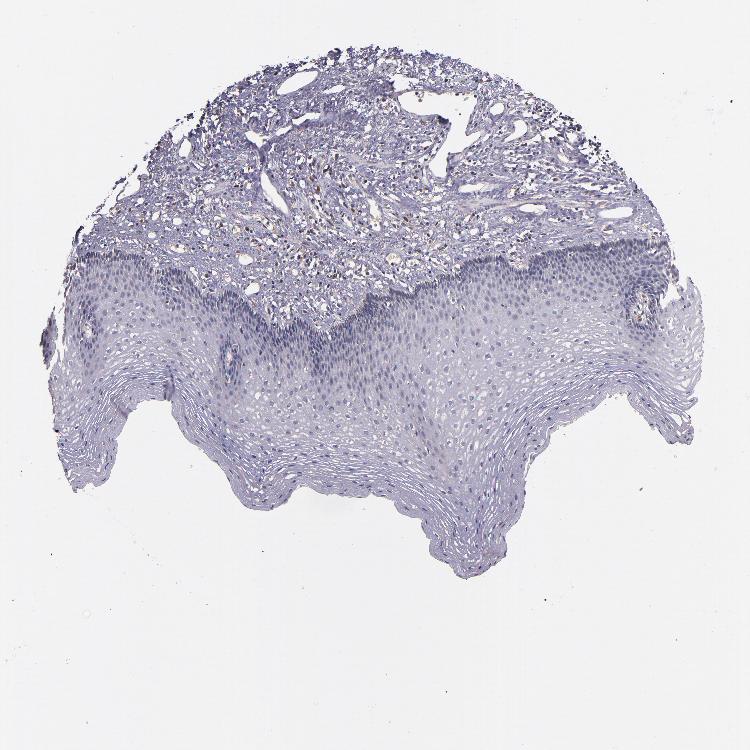

ESOPHAGUS - Antibody stainingi

Antibody staining in the annotated cell types in the current human tissue is reported as not detected, low, medium, or high, based on conventional immunohistochemistry profiling in selected tissues. This score is based on the combination of the staining intensity and fraction of stained cells.

Each image is clickable and will lead to virtual microscopy that enables deeper exploration of all samples and also displays staining intensity scores, fraction scores and subcellular localization as well as patient and tissue information for each sample.

Antibody HPA002859Antibody CAB011655

Squamous epithelial cells LowHigh